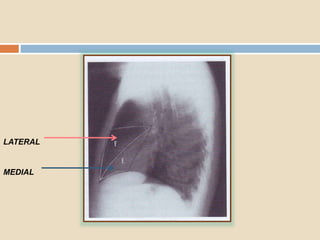

 El segmento lateral

está limitado por la

cisura menor en su

parte superior, tanto en

la placa PA como la

lateral.

 El segmento medial

está situado junto al

borde cardíaco derecho

, en su parte medial, y

contra la cisura mayor

en su parte posterior.

LATERAL

MEDIAL